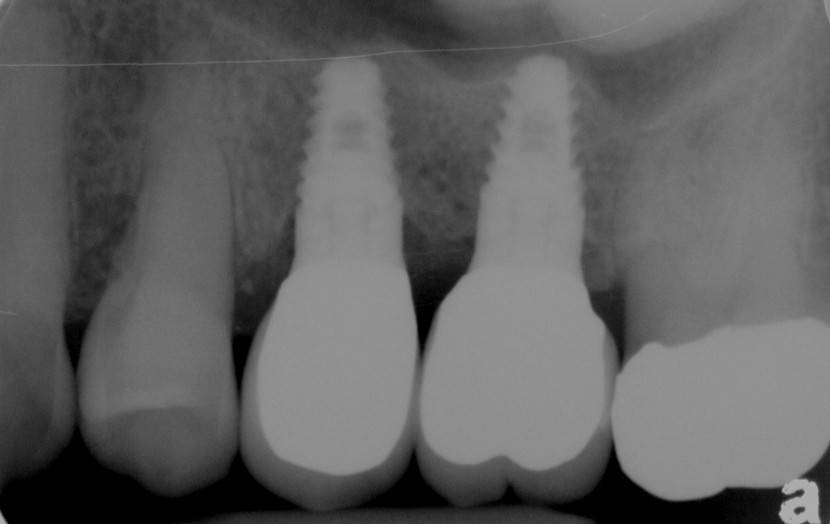

Nakon ugradnje implantata potrebno je vrijeme da bi se on integrirao, odnosno srastao sa kosti. Taj proces se naziva osteointegracija, a traje između 4 do 6 mjeseci. Kad u čeljusti uopće nemamo zubi možemo ih staviti u obliku fiksnog mosta na samo 4 implantata. To se zove sistem ALL-ON-FOUR.